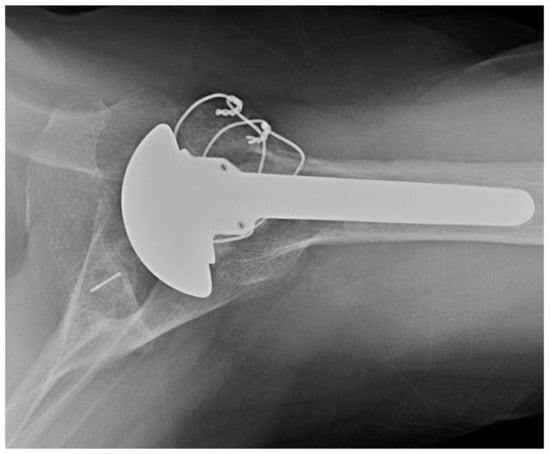

2.1.3. Convertible Platforms

4.1. Convertible Implants

4.2. Humeral Bone Loss